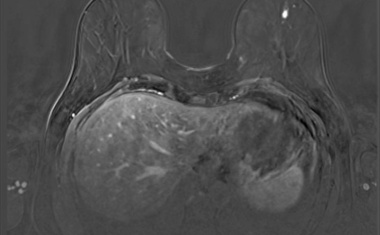

Dexamethason könnte Brustkrebs-Metastasen reduzieren

Das Medikament Dexamethason ergänzt Krebsbehandlungen, um Nebenwirkungen der Chemotherapie wie etwa Übelkeit und Entzündungen zu mildern. Forschende der Universität Basel haben nun entdeckt, dass es darüber hinaus auch Metastasen bei bestimmten Typen von Brustkrebs bekämpft.